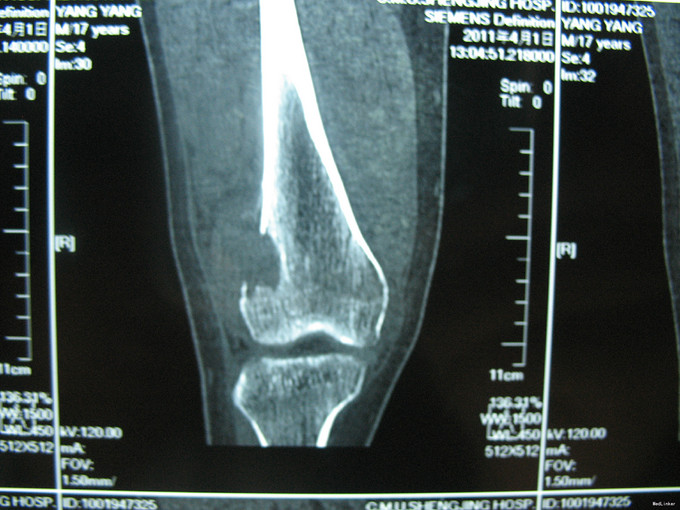

右膝上疼痛2个月肿胀一周 患者2个月前无明显诱因出现右膝上疼痛,逐渐加重,一周前活动后加重明显并开始出现肿胀,右膝关节活动受限,于当地医院行CT及MRI检查考虑为恶性肿瘤,遂来我院治疗。

入院后完善相关检查,诊断为股骨恶性肿瘤,考虑为骨肉瘤。切取部分肿物病理活检。病理明确诊断股骨骨肉瘤后,给予新辅助化疗。化疗效果明显,手术行瘤段切除人工假体置换术。